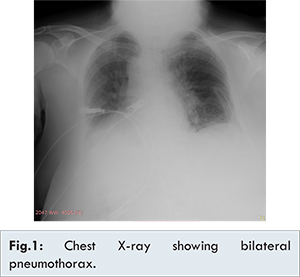

On completion of surgery, the intubated patient was transported to the imaging center. During transport, the patient received manual ventilation with a bag valve device, and was monitored with pulse oximetry. After she was brought back to the operating room, the neuromuscular block was reversed with atropine and neostigmine. The patient was extubated, when the respiration seemed adequate, and the conscious was recovered.  Her vital signs were stable (blood pressure: 135/75 mmHg, heart rate: 82 beats/min, and SpO2: 98%), so she was transferred to the postoperative recovery unit (PACU). Approximately five minutes after arrival, she developed dyspnea, chest pain, cyanosis, and severe agitation. During this period, the patient’s vital signs were: a SpO2 of 72%, a heart rate of 125 beats/min, and a blood pressure of 70/45 mmHg. The patient was oxygenated with a face mask (5 L/min), and was immediately transferred to the ICU for respiratory support. A portable chest X-ray, and CT were taken. The radiological examinations revealed a bilateral pneumothorax which was more prominent on the left side, and pneumo-mediastinum [Fig.1]. The left chest tube was placed, and the patient made a rapid recovery. On the third postoperative day, chest X-ray showed complete expansion of the lung, and the chest drain was removed. She was shifted to the ward, and was uneventfully discharged from the hospital on the sixth postoperative day.

In the postoperative period, PNX needs to be differentiated from bronchospasm, pulmonary embolism, pulmonary edema, and pulmonary aspiration. The most common presentations of PNX include tachycardia, chest pain, dyspnea, anxiety, decreased breath sounds, hypoxemia, and hypotension. In our case, she developed hypoxemia, dyspnea, tachypnea, chest pain, and tachycardia. During this period, the patient was oxygenated with face mask, and was immediately transferred to the ICU. A chest-X ray and CT scan thorax confirmed the presence of a bilateral pneumothorax and pneumo-mediastinum. The left chest drain was placed, and the patient made a good recovery rapidly. The patient was discharged uneventfully at the sixth postoperative day.